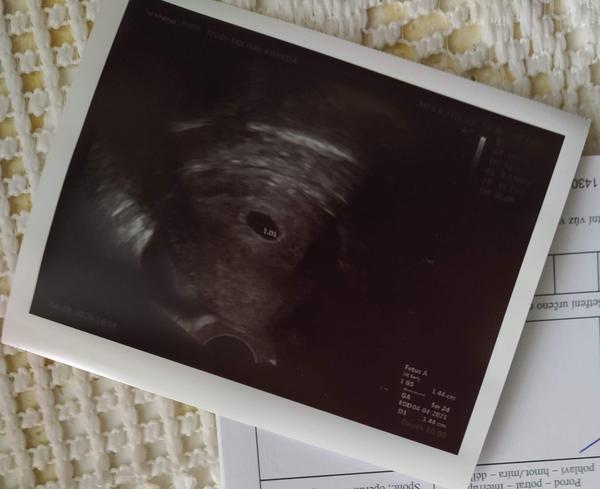

5.tt a gestační váček 5 mm. Je to v pořádku?

Ahoj, prosím o zkušenosti... Jsem v 5+2tt a na ultrazvuku šel vidět gestacni Vacek velikost 5mm je to v pořádku??? Nebo se mám bát... Už jsem po jednom ZT a teď mám strach... Děkuji za odpovědi 😉